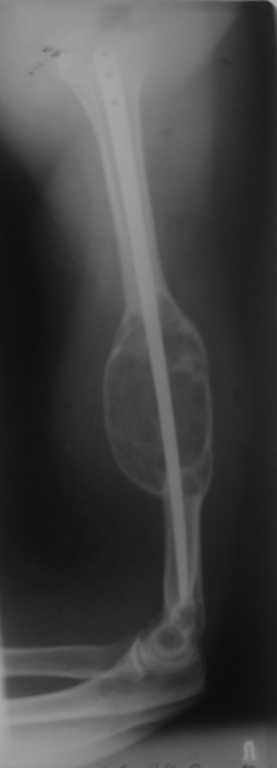

Уважаемые коллеги! 3 года назад оперирована пациентка по поводу патологического перелома плеча на фоне костной кисты. Выполнен ЗИО плоским титановым стержнем. Спустя 1,5 года на фоне сросшегося перелома выявлен рост опухоли, подозрение на малигнизацию. Консультирована онкологами, те пациентку своей не признали, биопсия не проводилась. Биопсия выполнена в июне 2009, по заключению одного учреждения - костная киста, по другому - хондросаркома. Обследована, отдаленных метастазов нет. Вопросы: Диагноз? Варианты лечения? Может резекция в пределах здоровой кости, каркасная металлопластика плюс гвоздь? Спасибо.

Мне кажется у Вас уже есть план лечения данной больной и помоему вполне правильный. Диагноз... наверное биопсию провести надо, хотя это больше для определения объёма оперативного вмешательства. Однозначно резекция в пределах здоровой кости, а далее - eсли есть время и желание, а главное настрой пациентки всевозможные варианты костной пластики. Если же позволяют возможности больной или лечебного учереждения сетчатый опорный кейдж с аутокостью, фиксированный блокированным стержнем с ранним функциональным восстановлением конечности.

Согласен с тактикой.Надо выполнить повторную биопсию,чтобы точно определиться,что там добро или зло?По идее,всего скорее это добро...нужно резецировать в пределах здоровой кости.Удалить плоский стержень,выполнить костную пластику аутокостью и идеально при возможности(наличия стержня или денег у больного) остеосинтез блокируемым стержнем в статическом варианте,восстановить длину сегмента,раннее восстановление функции суставов.Если блокированного стержня нет,то на плоском стержне будет нестабильность,дистальный отломок небольшой.Тогда надо менять фиксатор на пластину.Но это не лучший вариант.

Всё правильно вариантов множество, скорее всего доктору необходимо воспользоваться тем, что удобнее всего для конкретной ситуации в лечебном учереждении (когда мы дождёмся, возможности обсуждать то, что необходимо, а не то, что имеем?). Можно рассмотреть как вариант, я бы скорее в данном случае так и поступил.Стержень - а учитывая поперечные линии контакта кости и импланта, установку скоб-стяжек (можно и с кольцевидным захватом с памятью формы) между центральным фрагментом и имплантом между имплантом и периферическим фрагментом, решается вопрос и с межфрагментарной компрессией. Вопрос малоинвазивности неактуален - всё равно опухоль удалять.